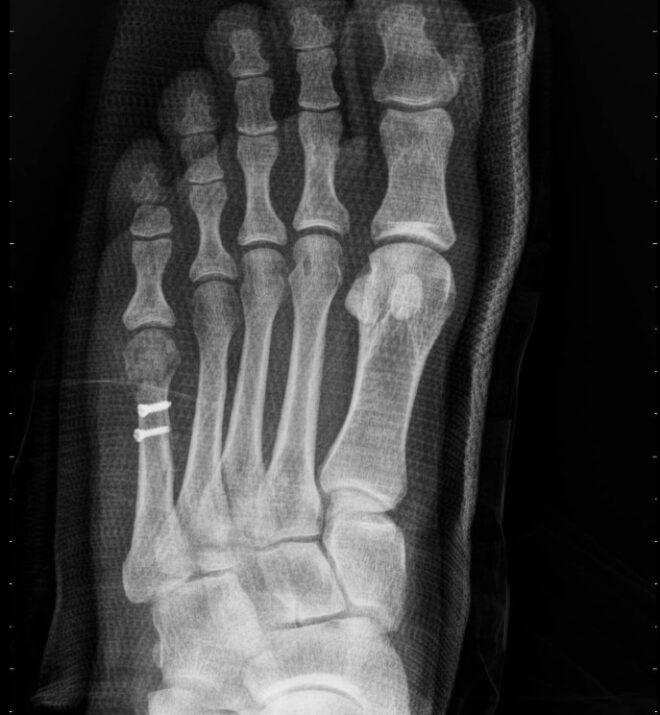

درمان شکستگی شافت متاتارس پنجم “رقصنده باله” معمولاً بدون عمل جراحی انجام میشود. درمان شامل استراحت نسبی و زمان برای بهبودی شکستگی است. به طور معمول ، برای بیماران یک گچ کوتاه گرفته میشود و برای چند هفته اول ، آنها باید راهپیمایی خود را به میزان قابل توجهی محدود کنند و ممکن است به عصا (شکل ۳) احتیاج داشته باشند.

جراحي به ندرت مورد نياز است اما در صورت جابجايي كامل قطعات شكستگي يا عدم بهبودي در درمان غير جراحي ممكن است لازم باشد. در این موارد ، قطعات استخوان با پیچ و یا یک صفحه دوباره جابجایی و تثبیت می شوند.